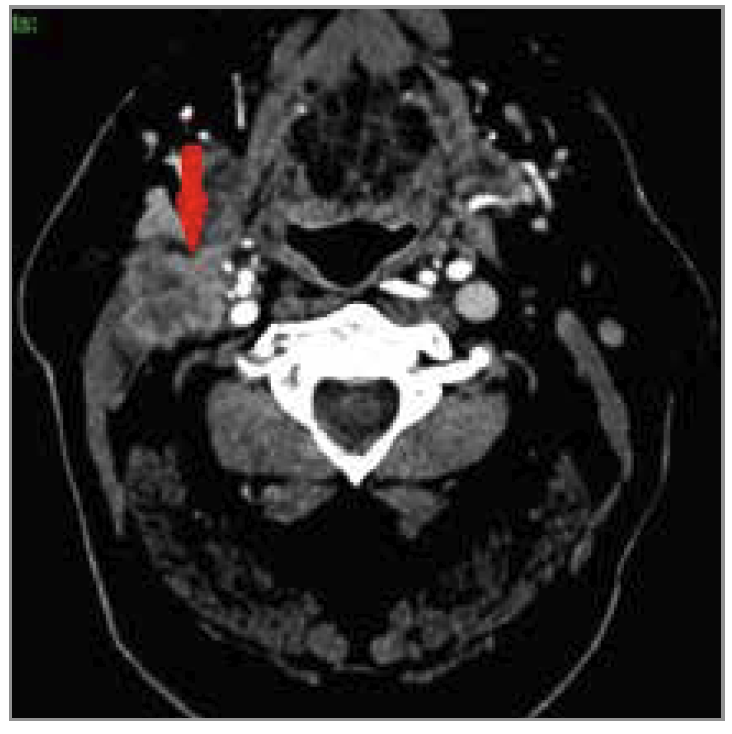

Le bilan ORL n’a pas permis d’identifier de lésion maligne au niveau de l’oropharynx, du rhinopharynx, ni de l’hypopharynx. Cependant, le scanner cervical a confirmé la présence d’une adénopathie très fortement suspecte, du fait de sa morphologie, d’un processus néoplasique (Fig. 2).

Figure 2 – Adénopathie suspecte au niveau cervical droit sur le scanner

Une biopsie de cette dernière a été effectuée et le diagnostic de carcinome épidermoïde de la cavité buccale a été posé avec un traitement associant radiothérapie et chimiothérapie.